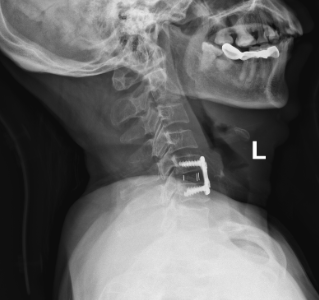

省医帮扶丨颈椎病在佛冈人医不再“束手无策”!

在现代快节奏的生活中,颈椎问题已经成为许多人的“隐形杀手”。颈部疼痛、上肢麻木无力等症状,不仅影响着我们的日常生活质量,还可能对健康造成威胁。然而,随着医学技术的不断进步,颈椎前路椎间盘摘除术为我们提供了有效的解决方案。

颈椎前路椎间盘摘除术是一种精准、高效的治疗方案,专门针对颈椎间盘突出、退变等严重问题。这项手术创伤相对较小,大大降低了手术风险和术后并发症的发生概率。

骨科一区主要治疗病种有:(1)颈肩腰腿痛(2)脊柱损伤(3)骨盆骨折(4)下肢疾病。能开展的手术有:颈/腰椎微创、开放手术,骨盆及下肢骨折内固定、肿瘤切除等手术。